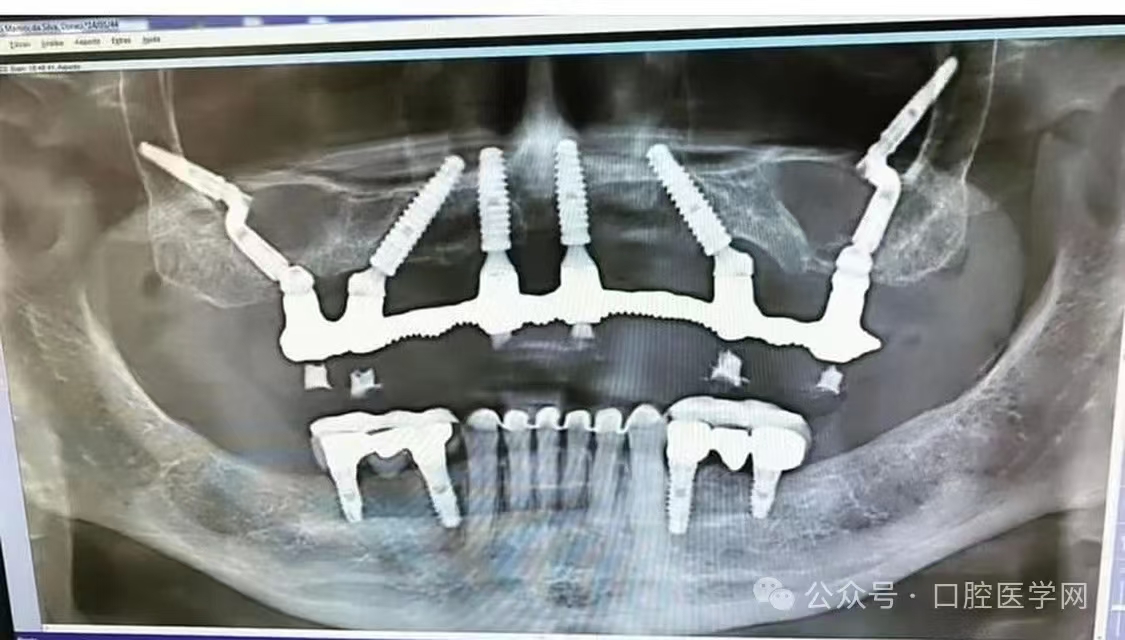

这是什么种植方法?